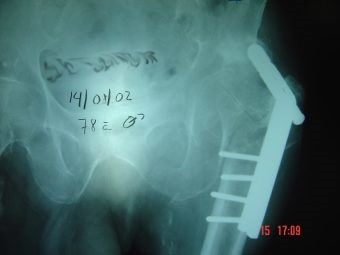

Prótesis Total de Cadera por Fractura

Envíado por Dr. Ricardo Antonio Gómez G.